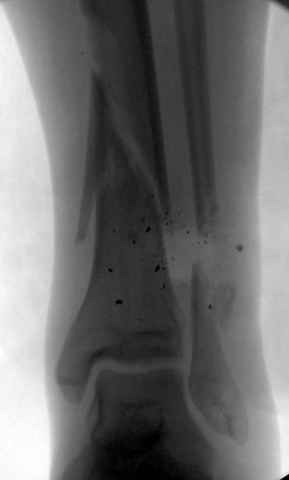

На снимках варианты фиксации малоберцовой:

№ 6-11 при pilon percutaneus fixation